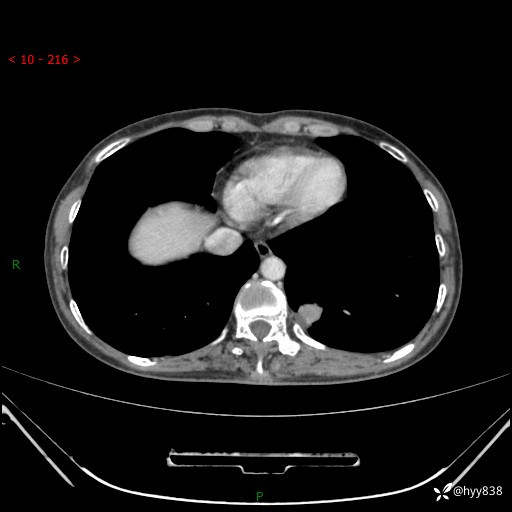

胸部CT平扫

增强动脉期+静脉期

各期CT值:48hu 65hu 76hu